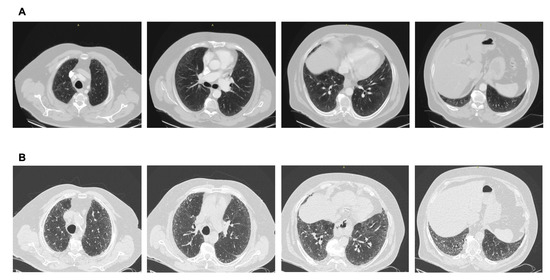

Figure 3. (A) CT scan performed after a car accident in an asymptomatic individual. Note the mild ground glass subpleural changes and the subtle mosaic attenuation. No investigation/intervention followed. (B) Three years later, the patient became symptomatic, with remarkable progression to a fibrotic pattern. A heavy exposure to pigeons was revealed. Final diagnosis: Hypersensitivity pneumonitis. Avoidance of the causative factor would possibly have attenuated progression.